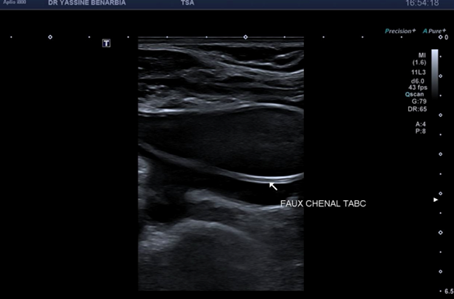

Du côté droit, l'examen met en évidence une dissection du tronc brachiocéphalique (TABC) avec présence d'un faux chenal circulant. Le flap intimal est clairement visible en mode B, séparant le vrai chenal du faux chenal. Au Doppler couleur, on observe un double flux avec des vélocités différenciées : le vrai chenal présente un flux rapide (codé en bleu qui s’éloigne de la sonde) tandis que le faux chenal montre un flux plus lent (codé en rouge qui se rapproche de la sonde).

Les signes retrouvés à l'échographie-Doppler sont : flap intimal mobile visible en mode B séparant vrai et faux chenal, double lumière artérielle en coupe transversale et longitudinale, flux différenciés au Doppler couleur (vélocités élevées dans le vrai chenal, flux plus lent dans le faux chenal), et spectre Doppler pulsé conservé dans le vrai chenal (triphasique ou biphasique).